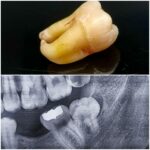

ایمپلنت مجموع قطعاتی است که با جراحی داخل فک ثابت میشوند روی آن دندان مصنوعی قرار میگیرد و در نهایت ظاهری مشابه با دندان طبیعی پیدا میکند.

بهطور کلی برای گذاشتن ایمپلنت دندان چندین مرحله باید انجام شود تا قطعات تشکیل دهنده در کنار یکدیگر قرار گیرند و بیمار بتواند به جای دندان طبیعی از آن استفاده کند. ایمپلنت از نظر ظاهری مشابه دندان طبیعی است و در دهان همان حس طبیعی را برای جویدن القا میکند و سوء هاضمه ایجاد شده بر اثر ناتوانی در جویدن غذا را برطرف مینماید.

ایمپلنت دندان برای جایگزین کردن یک یا چندین دندان از دست رفته کاربرد دارد و میتواند برای تمام دندانها به صورت ثابت یا متحرک استفاده شود. در هر دو حالت فوق کلمه ایمپلنت استفاده میشود اما حالت دوم بیانگر معنی واقعی ایمپلنت است و به مجموعهای از قطعات ایمپلنت گفته میشود و هر کدام از قطعات به تنهایی نام و کارایی مجزایی دارند.